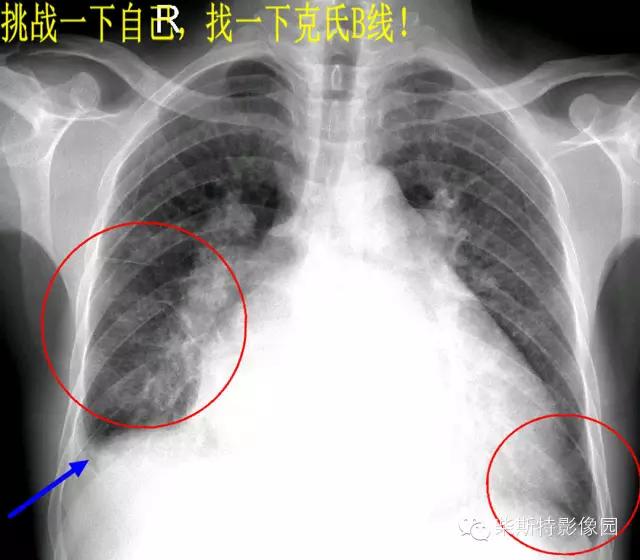

经典图像第二例:

大家找到克氏B线了吗?

2.B线:为克氏线征中最常见者,表现为较短的不分又的梯状致密横线影,长不超过2cm,宽不超过1mm。常位于两下肺野的外带(肋隔角)平行的次出现,亦可见于中肺野,但从不出现于上肺野。其外端常抵达胸膜缘并与之垂直,以右侧为多见.